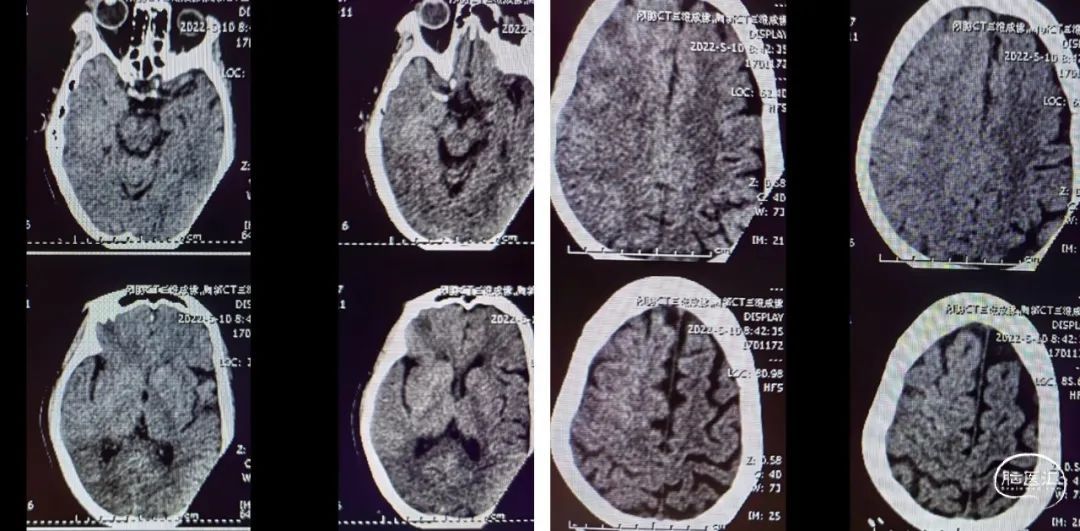

入院影像检查

MRI+DWI

重要影像结论:右侧放射区、右侧基底节区、左侧额叶近大脑镰处多发急性梗死。

重要影像结论:右侧颈内动脉岩骨段管腔内不清晰,眼动脉段远端管腔较对侧明显缩小。

重要影像结论:右侧ICA起始部急性闭塞,前交通动脉、后交通动脉未开放。

(术后8h CT)右侧放射冠区、右侧基底节区、右侧额叶多发急性梗死。

(术后7d CT)右侧放射冠区、右侧基底节区、右侧颞叶、额叶多发急性梗死。

(术后14d CTA)RMCA-M1支架植入术后改变。